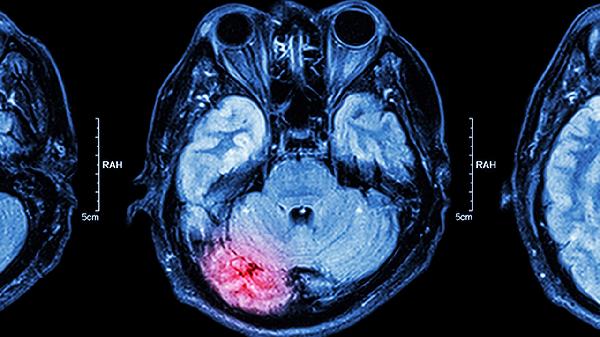

通过扩张脑血管、降低血液黏稠度等机制,可增加脑组织血氧供应。适用于脑血管痉挛、慢性脑缺血引起的记忆力减退、注意力不集中等症状,辅助用药包含盐酸氟桂利嗪胶囊、尼莫地平片等钙通道阻滞剂。